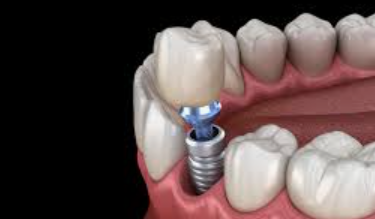

어금니 임플란트 과정

어금니 임플란트의 과정은 여러 단계로 구성되어 있습니다. 어금니 임플란트 가격을 고려한 후, 아래의 단계를 참고하시면 됩니다.

2단계 - 수술: 치과 의사는 어금니 부위에 조심스럽게 구멍을 내고 임플란트를 삽입합니다. 그 후, 임플란트 주위의 뼈와 임플란트가 안정적으로 결합되도록 치유를 위한 기간을 마련합니다. 이 과정은 일반적으로 수 주에서 몇 개월까지 소요될 수 있습니다.

3단계 - 임시 크라운 부착: 치유 기간 이후, 임플란트와 주변 뼈가 충분히 결합된 것으로 판단되면 임시 크라운을 임플란트에 부착합니다. 이를 통해 환자는 정상적인 식사와 말하기를 할 수 있게 됩니다.

4단계 - 영구 크라운 설치: 뼈와 임플란트가 완전히 결합된 후, 임시 크라운을 제거하고 영구 크라운을 설치합니다. 이 단계에서는 어금니의 자연스러운 외관과 느낌을 제공하여 장기적으로 안정성과 기능성을 보장합니다.